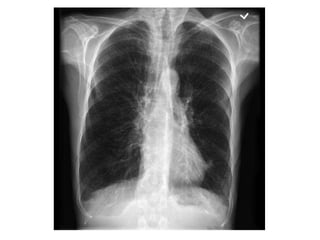

COPD

Normal COPD

R